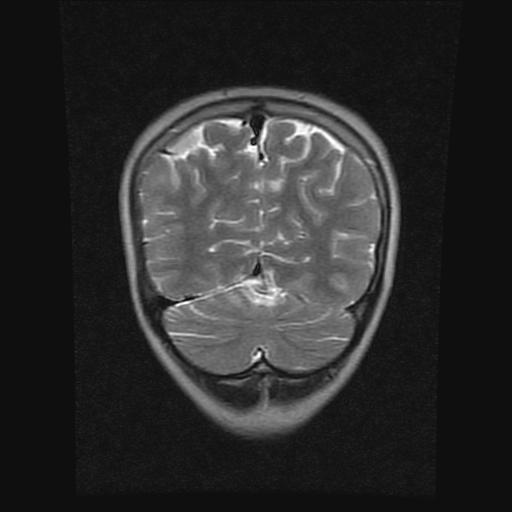

9岁女孩,三岁时诊断为癫痫,一直服丙戊酸钠,现患者一般情况良好,家长复查核磁片,看能否停药..

巨脑回

停药要结合临床,如无发作可以停。

停药要结合临床,如无发作可以停